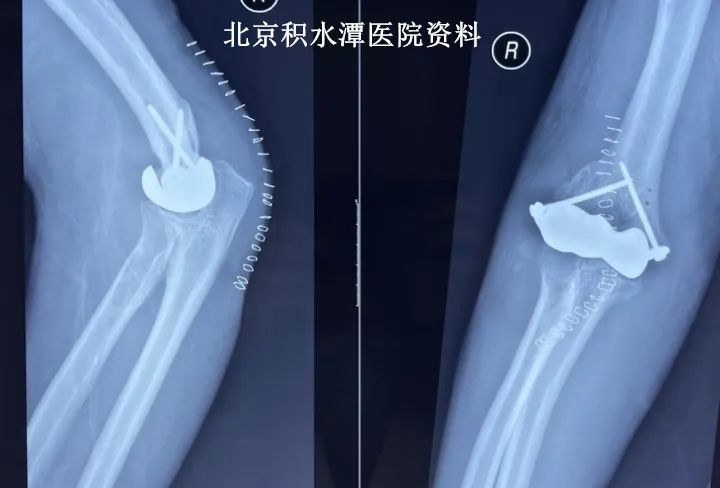

石膏制动三周后,2022年8月9日,老张和家人来复查,拆除石膏并拆线,假体位置满意,关节对合良好,医生开始指导他活动,主动活动可达屈肘100度,伸肘40度,被动活动屈肘可达130度,伸肘30度,旋后基本正常,旋前略受限,检查关节稳定性良好。

患者术后三周拆石膏时的X光片和主动活动体位相